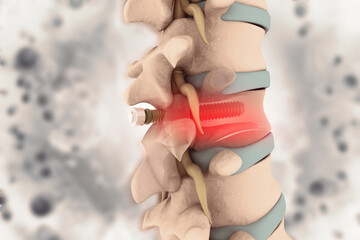

A Novel Jig to Assist Accurate Insertion of S2AI Screw

Medical Devices